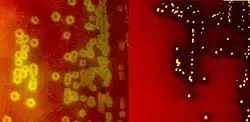

Species of streptococci are classified based on their hemolytic properties.[10] Alpha-hemolytic species cause oxidization of iron in hemoglobin molecules within red blood cells, giving it a greenish color on blood agar. Beta-hemolytic species cause complete rupture of red blood cells. On blood agar, this appears as wide areas clear of blood cells surrounding bacterial colonies. Gamma-hemolytic species cause no hemolysis.[11]

When alpha-hemolysis (α-hemolysis) is present, the agar under the colony will appear dark and greenish due to the conversion of hemoglobin to green biliverdin. Streptococcus pneumoniae and a group of oral streptococci (Streptococcus viridans or viridans streptococci) display alpha-hemolysis. Alpha-hemolysis is also termed incomplete hemolysis or partial hemolysis because the cell membranes of the red blood cells are left intact. This is also sometimes called green hemolysis because of the color change in the agar.

Beta-hemolysis (β-hemolysis), sometimes called complete hemolysis, is a complete lysis of red cells in the media around and under the colonies: the area appears lightened (yellow) and transparent. Streptolysin, an exotoxin, is the enzyme produced by the bacteria which causes the complete lysis of red blood cells. There are two types of streptolysin: Streptolysin O (SLO) and streptolysin S (SLS). Streptolysin O is an oxygen-sensitive cytotoxin, secreted by most group A Streptococcus (GAS), and interacts with cholesterol in the membrane of eukaryotic cells (mainly red and white blood cells, macrophages, and platelets), and usually results in beta-hemolysis under the surface of blood agar. Streptolysin S is an oxygen-stable cytotoxin also produced by most GAS strains which results in clearing on the surface of blood agar. SLS affects immune cells, including polymorphonuclear leukocytes and lymphocytes, and is thought to prevent the host immune system from clearing infection. Streptococcus pyogenes, or GAS, displays beta hemolysis.